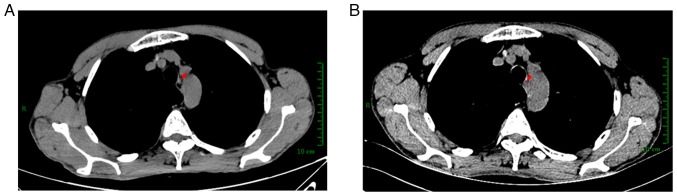

Immunotherapy provides durable responses for locally advanced esophageal carcinoma clinical therapy in numerous patients. However, the mechanisms of resistance to immunotherapy have not been elucidated. The phenomenon of the histological transformation of non-small cell lung cancer to small cell lung cancer resulting in resistance to immune checkpoint inhibitors (ICIs) has been reported. It remains unclear whether ICIs or chemotherapy could cause a similar transformation from esophageal squamous cell carcinoma (ESCC) to esophageal neuroendocrine carcinoma (ENEC). The present study report the case of a patient initially diagnosed with stage II ESCC who underwent radical surgery after three cycles of neoadjuvant therapy with cisplatin, albumin bound paclitaxel and ICIs. Immunohistochemical staining confirmed the absence of the SCC component and the presence of the NEC component, with negativity for CK5/6 and tumor protein p40, but positive expression of tumor protein p53, pan-cytokeratin, synaptophysin and CD56. The patient was followed up for 5 months with no treatment or postoperative complications. In conclusion, histological transformation to ENEC is a potential mechanism of acquired resistance to ICIs in ESCC. Prospective larger studies are warranted to further characterize ESCC-to-NEC transformation on use of ICIs.